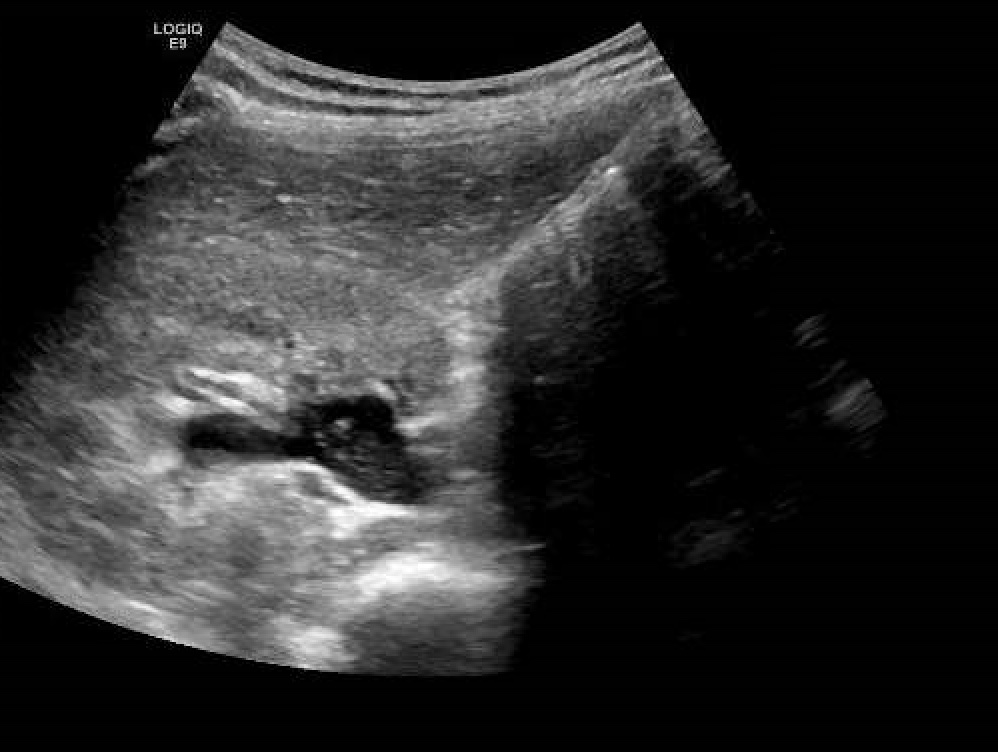

Hallazgos ecográficos

Ecografía abdomen: Dilatación moderada de ureter derecho proximal y parte de pelvis renal (14 mm) sin posibilidad de visualización de litiasis por gestación. Vejiga deplecionada. Movimientos fetales activos con latido conservado.

Juicio clínico: Hidronefrosis moderada por compresion uterina (embarazo).